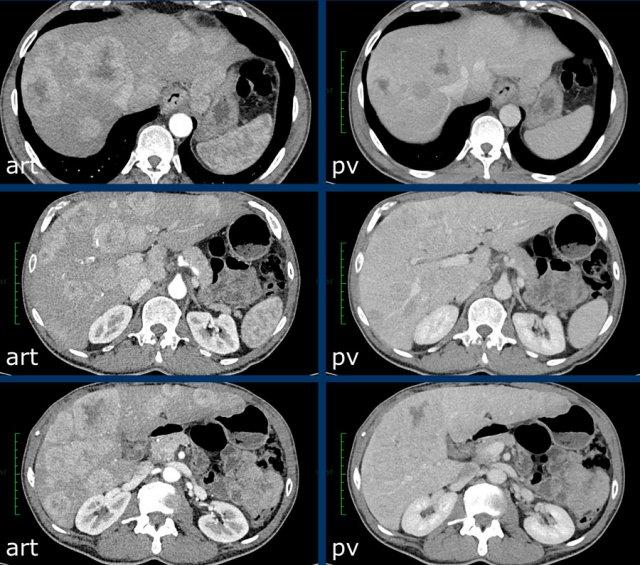

Kích thước cũng là yếu tố quyết định tổn thương được xếp vào phân loại nào.

Tổn thương càng lớn, khả năng là HCC càng cao.

Tổn thương cần được đo trong thì, chuỗi xung hoặc mặt phẳng mà bờ tổn thương hiện rõ nhất.

Nên tránh đo kích thước trên thì động mạch và chuỗi xung DWI vì kích thước có thể bị ước tính quá mức do hiện tượng tổng hợp ngấm thuốc quanh tổn thương và biến dạng giải phẫu tương ứng.

Tăng trưởng vượt ngưỡng cũng là một dấu hiệu quan trọng.

Được định nghĩa là tăng kích thước hơn 50% trong vòng dưới 6 tháng.

Các hình ảnh cho thấy một tổn thương tại phân thùy 5 của gan có biểu hiện tăng ngấm thuốc thì động mạch.

Tổn thương đã tăng kích thước từ 8 mm lên 21 mm trong 3 tháng, đáp ứng tiêu chí tăng trưởng vượt ngưỡng.